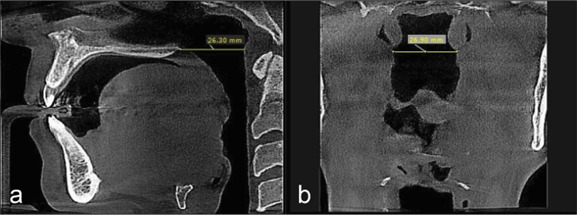

Materials and method: In this retrospective cross-sectional study, cone beam computed tomography (CBCT) records of 100 patients were analyzed. Patients were snoring non-OSA individuals, diagnosed through a thorough examination and negative polysomnography results. CBCT scans were executed in the standard position as per the specified protocol of the Sleep Center. Upper airway was divided into four parts (nasopharynx, velopharynx, oropharynx, and hypopharynx), and anteroposterior (AP) and transverse (T) dimensions within the minimal cross-sectional area of each respective region were evaluated. BMI, upper airway dimension, and hyoid bone were analyzed using Pearson and Spearman's correlation tests.

Results:  The retrognathion-hyoid-4th cervical vertebra (RHV) angle representative of the hyoid position was significantly greater in females (p Value=0.000). It also statistically decreased significantly in snorers aged 36-50 and 51-65, p= 0.006 and 0.012, respectively. Snorers had above-average BMI in all age groups and both genders. The AP-hypopharynx significantly correlated with BMI (p= 0.022).

Conclusion:  The hyoid position was gender-dependent, with a superior position in females. It was also age-dependent, with a more inferior position in snorers aged 36-65 compared to younger ages (20-35). The AP-velopharynx is a constriction region in the airway of snorers. Snorers were overweight in all age groups and both genders. BMI had a significant correlation with the AP-hypopharynx.